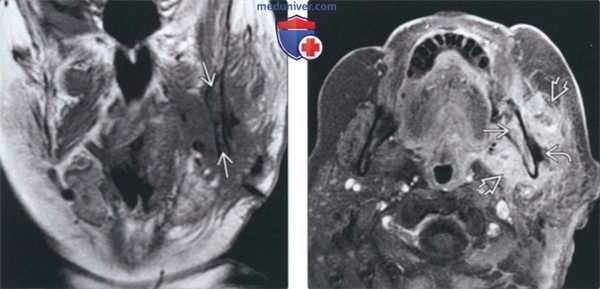

(Слева) На корональной МРТ (Т1 ВИ) у пациента 79 лет с рецидивирующим абсцессом жевательного пространава через 12 недель после установления диагноза и дренирования определяется тотальное замещение гиперинтенсивного сигнала в жировом костном мозге нижней челюсти слева, сопоставимое с остеомиелитом.

(Справа) На аксиальной MPT (Т1ВИ С+) с жироподавлением у этого же пациента определяется диффузное контрастное усиление костного мозга и жевательного пространства (флегмона) слева. Определяется небольшой абсцесс в наружных отделах.

(Слева) Корональная МРТ в режиме Т1 у пациента 79 лет с рецидивом абсцесса жевательного пространства спустя двенадцать месяцев после того, как он был обнаружен и дренирован. Гиперинтенсивный сигнал, которым характеризуется костный мозг в норме, в нижней челюсти слева не определяется: изменения обусловлены остеомиелитом. Обратите внимание на отек медиальной крыловидной и жевательной мышц.

(Справа) При МРТ Т1ВИ FS c КУ в аксиальной проекции у этого же пациента определяется диффузное накопление контраста в коаном мозге слева, а также в жевательном пространстве (флегмона); виден небольшой абсцесс снаружи от нижней челюсти.

5. МРТ при остеомиелите челюсти:

• Т1 ВИ:

о Потеря сигнала на Т1 по мере замещения костного мозга экссудатом (острая фаза) или фиброзом/склерозом (хроническая фаза)

• STIR:

о Острая фаза: выраженный гиперинтенсивный сигнал в костном мозге, обусловленный отеком или гиперемией

о Хроническая фаза: сигнал варьирует в зависимости от выраженности фиброза и склероза

о Воспаление окружающих мягких тканей обнаруживается благодаря гиперинтенсивному сигналу

• Т1 ВИ С+ FS:

о Острая фаза: выраженное контрастное усиление костного мозга

о Хроническая фаза: контрастное усиление различной выраженности

о Контрастное усиление окружающих мягких тканей, особенно жевательных мышц